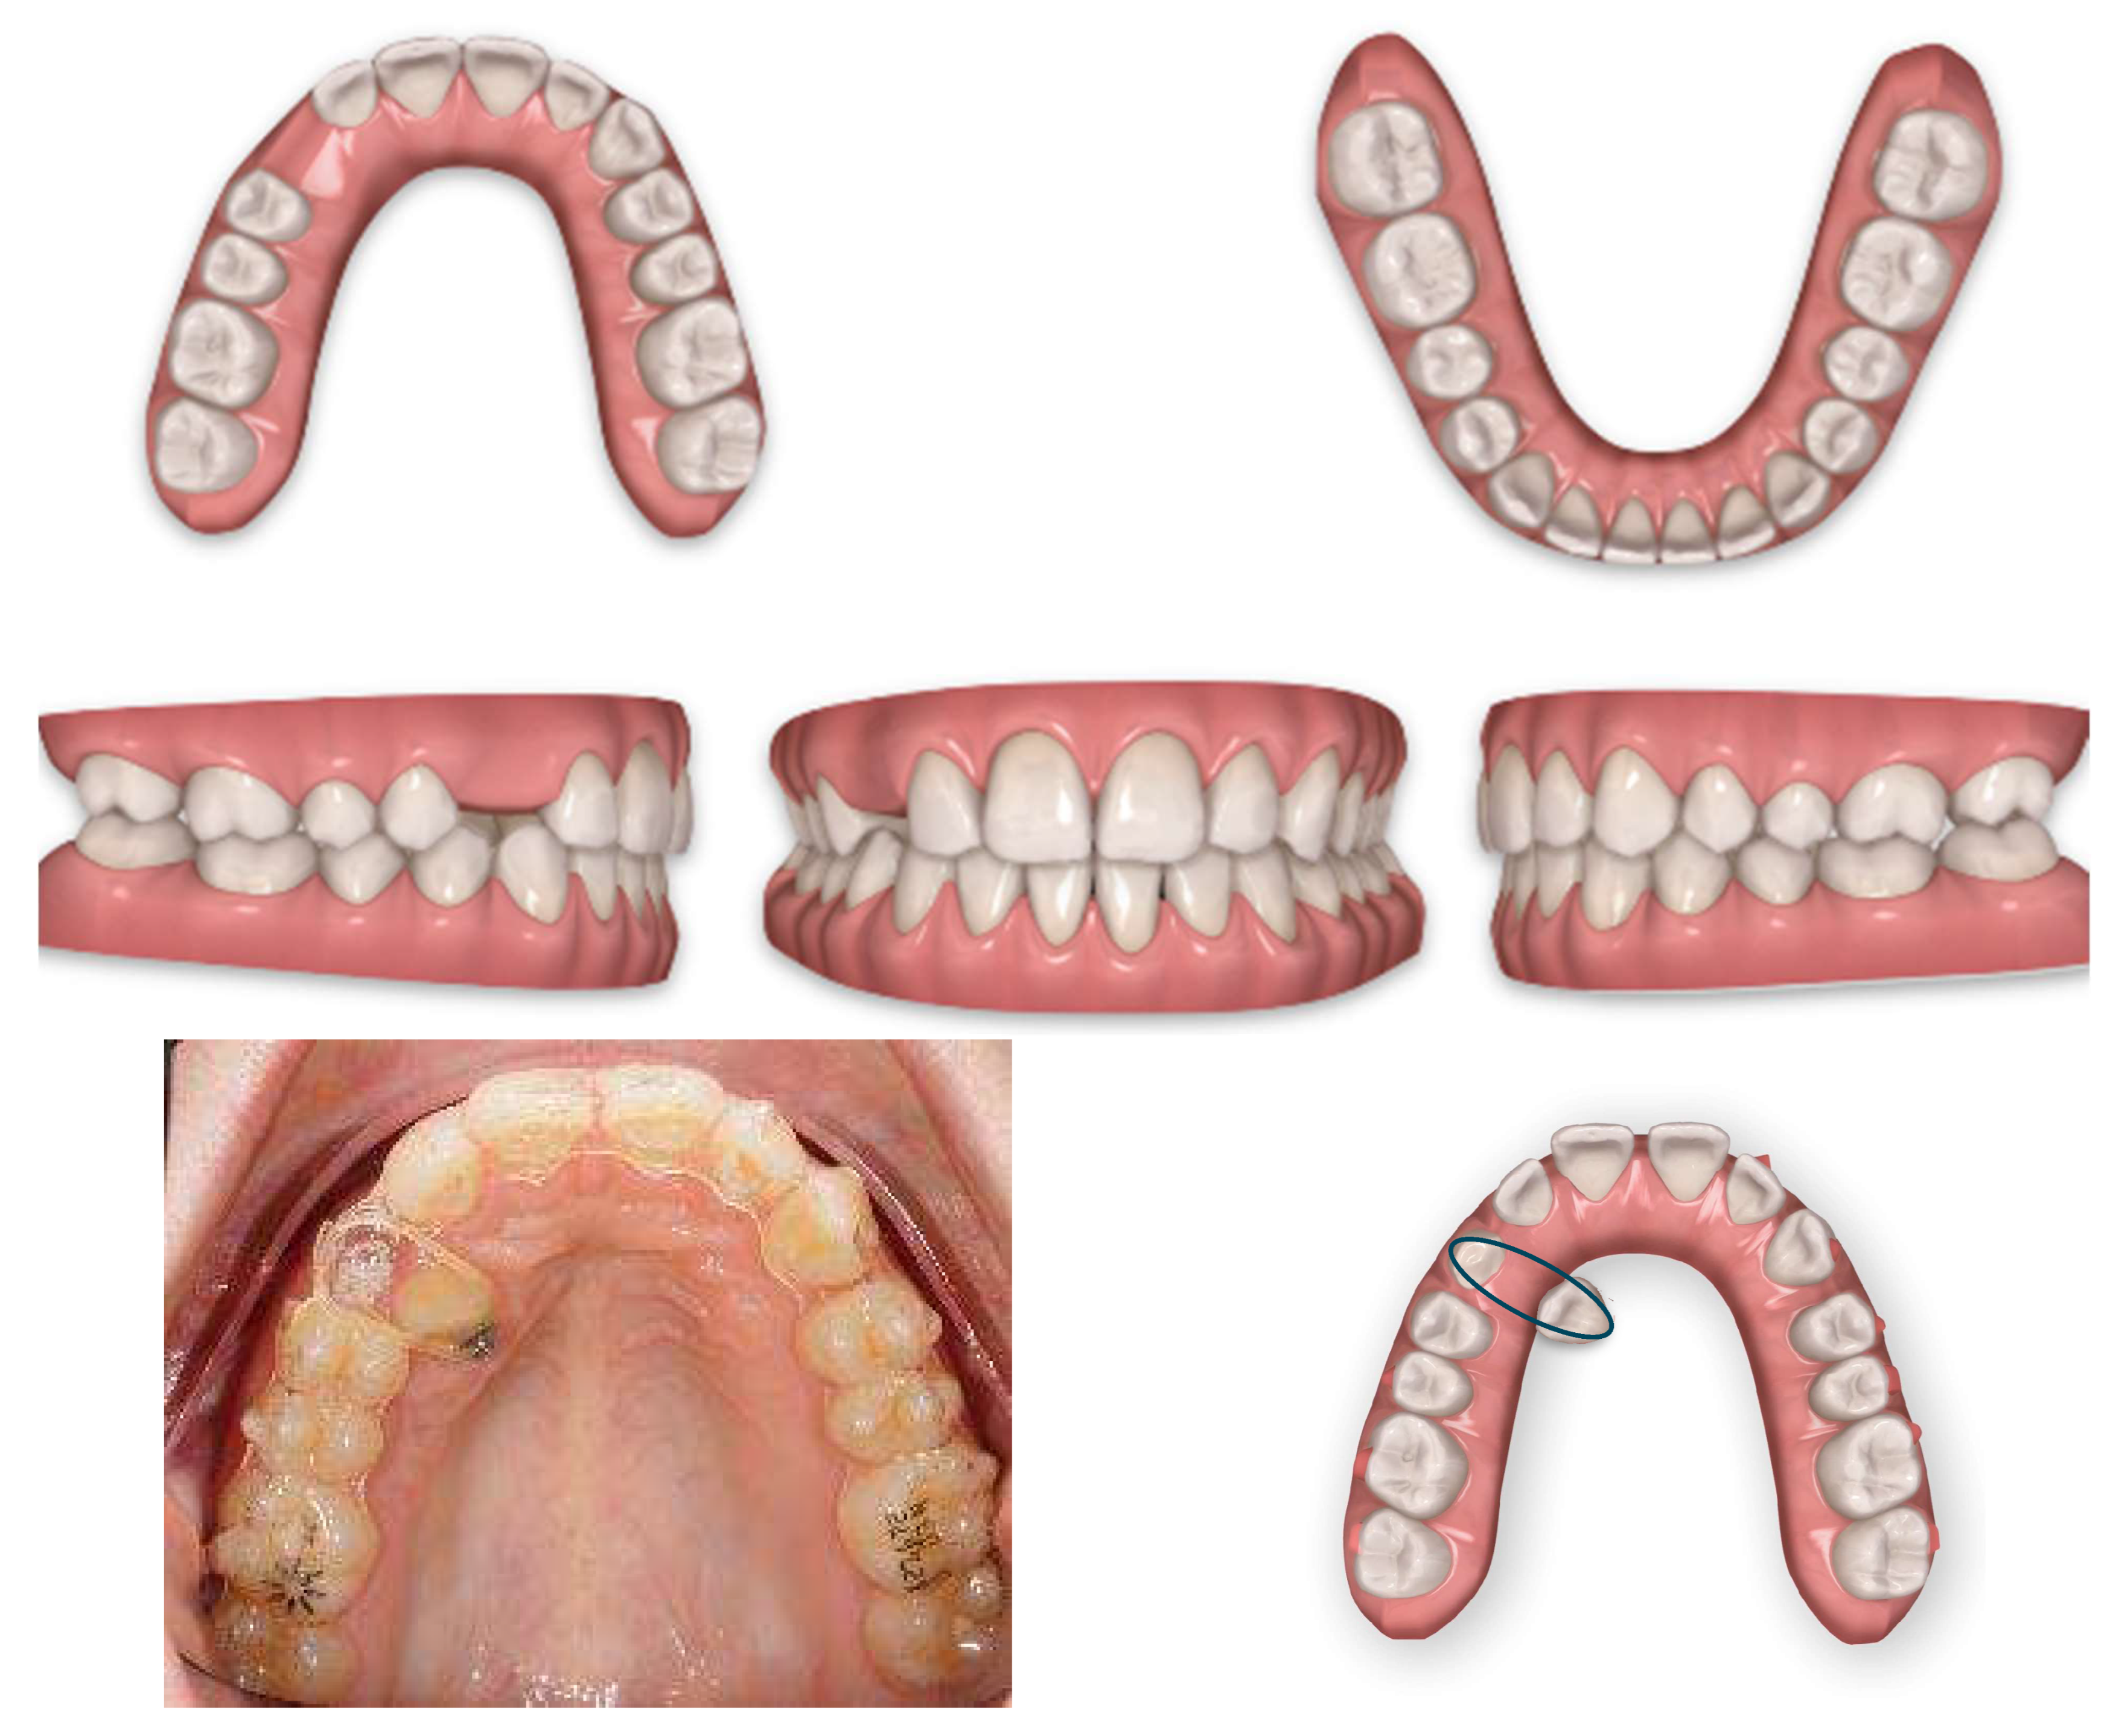

Post-treatment records of the patient successfully treated using a combination of cantilever mechanics with TADs and clear aligners show a control of the facial aesthetics from the frontal and lateral perspectives with a harmonious soft-tissue profile. Final clinical records show good aesthetics and the functional recovery of the upper canines in the arch. A Class I canine relationship was achieved, and overbite and overjet were normalized. The correction of crowding was carried out (Figure 17).

Figure 17.

Post-treatment extraoral and intraoral pictures.

At the end of the treatment, cephalometric radiographs show the good control of the upper and lower inclination. The radiographic evaluation shows an ideal root parallelism and a preserved periodontal health in the canine region (Figure 18). Retention was achieved through Vivera in the upper arch and via a bonded lingual retainer in the lower arch. No TAD failures were observed.

Figure 18.

Final radiographs and landmarks.